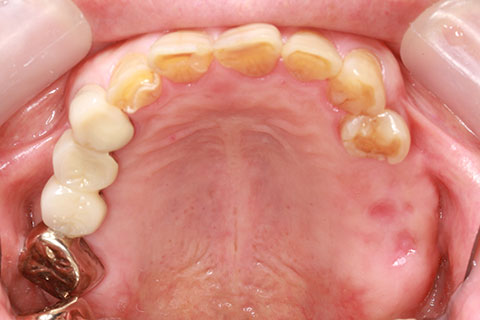

• 症例3

治療前

インプラント埋入時

治療後

年齢・性別

60歳男性

治療期間

2ヶ月

抜歯

なし

治療費

61.6万円

備考

右下6.7欠損

治療内容

右下6.7欠損部にインプラント埋入

施術の副作用(リスク)

オペによる知覚障害。インプラントによる歯肉炎。インプラント脱落。